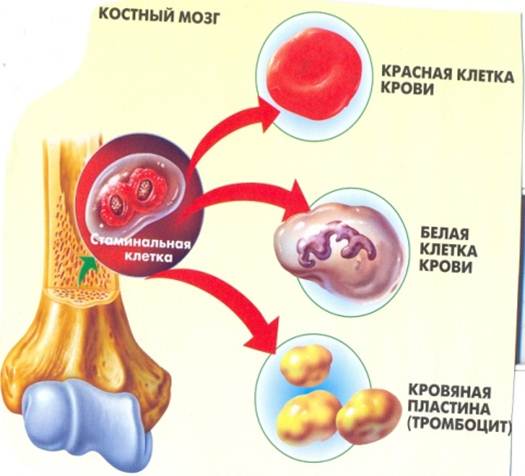

Изучение костного мозга: анатомия и функции